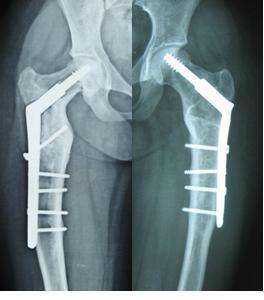

骨纖維結(jié)構(gòu)不良又稱骨纖維異樣增殖癥。臨床常見(jiàn)的骨發(fā)育異常,占骨腫瘤樣病變的38.42%,居首位,是肋骨最常見(jiàn)的良性病變。分為單骨型(85%)和多骨型(15%),多骨型伴內(nèi)分泌紊亂和皮膚色素沉著,為麥-奧(McCune-Albright)綜合征。